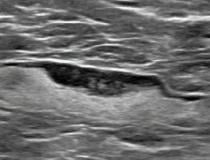

This photo gallery shows the variety of radiological presentations of COVID-19 (SARS-CoV-2) in medical imaging, including computed tomography (CT), radiograph X-rays, ultrasound, echocardiograms and magnetic resonance imaging (MRI). The radiology images show examples of typical COVID pneumonia in the lungs and the numerous complications the virus causes in the body in multiple organs, including the brain, kidneys, heart, abdomen and vascular system.

Ultrasound, especially hand-held ultrasound imaging devices, have become a primary imaging modality for novel coronavirus because of the ease to bag the device and sterilize it after use. CT and mobile X-ray systems are also used as front-line imaging systems for COVID-positive or suspected COVID patients.